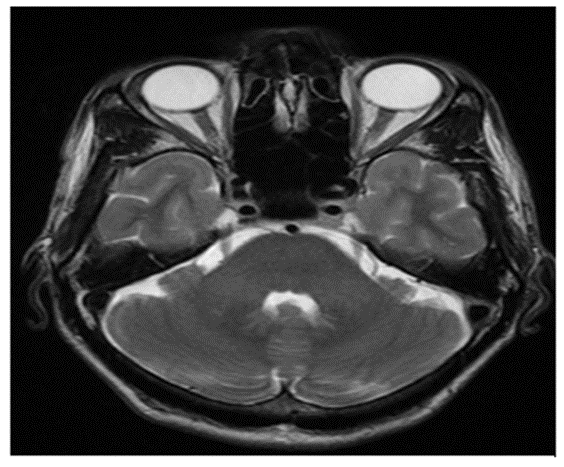

Female patient aged 39 years old presented with left trigeminal neuralgia in the distribution of the mandibular branch in the last 10 months. Neurological examination of the patient was within normal and VAS score was 7. Blink reflex was normal. MRI and MRA showed no evidence of secondary causes of TN or vascular contact (Fig. 3).

Figure 3: Normal MRI brain